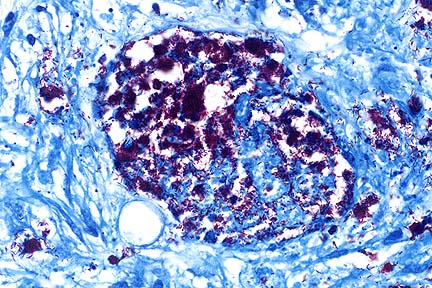

Mesenteric granuloma containing abundant acid-fast rod-shaped bacilli in a DSH with disseminated Mycobacterium avium-intracellulare infection. (Ziehl-Nielsen, 400X, 63K)

Higher magnification of the field above showing macrophages containing numerous acid-fast bacilli characteristic of M. avium-intracellulare infection. (

AFIP Diagnosis: Mesentery: Mesenteritis, granulomatous and necrotizing, chronic, focally extensive, severe, with intrahistiocytic acid-fast bacilli, Domestic Shorthair, feline.

Conference Note: Mycobacterium avium and Mycobacterium intracellulare share many of the same properties making distinquishing them difficult. For this reason, the causative organisms are often referred to as M. avium-intracellulare complex or MAIC.

Dogs and cats are believed to be very resistant to infection with MAIC. These organisms are ubiquitous saprophytic opportunists and tend to cause disease in immunocompomised patients. Disseminated infection in cats has been rarely reported. In all cases, the cats tested negative for FeLV antigen and FIV antibody. However, an immune deficiency has been implicated. Siamese cats may have a more generalized predisposition to infection with intracellular organisms. Genetic susceptibility to mycobacteria has been identified in humans, rabbits, Basset hounds, and mice. In some families of inbred mice, genetic susceptibility to mycobacteria is associated with a single autosomal gene, Bcg, that shares a locus with a gene coding for resistance to two other intracellular pathogens.

In most mammals, MAIC infections are characterized by a diffuse granulomatous, inflammatory reaction characterized by large numbers of macrophages filled with numerous intracytoplasmic bacilli without necrosis, fibrosis, or calcification. Multinucleate giant cells of the Langhans type are often present. There is usually little lymphocytic response. Lesions are usually multifocal and coalescing or diffuse. Regional lymph nodes are typically involved and infection may become generalized via the hematogenous route. In this case, emboli of necrotic material and bacteria were noted within vascular structures.